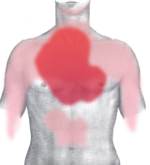

| Diagram of a myocardial infarction (2) of the tip of the anterior wall of the heart (an apical infarct) after occlusion (1) of a branch of the left coronary artery (LCA, right coronary artery = RCA). | |

Classical symptoms of acute myocardial infarction include sudden chest pain (typically radiating to the left arm or left side of the neck), shortness of breath, nausea, vomiting, palpitations, sweating, and anxiety (often described as a sense of impending doom). Women may experience less typical symptoms than men, most commonly shortness of breath, weakness, a feeling of indigestion, and fatigue. Approximately one quarter of all myocardial infarctions are silent, without chest pain or other symptoms. A heart attack is a medical emergency, and people experiencing chest pain are advised to alert their emergency medical services, because prompt treatment is beneficial.

The onset of symptoms in myocardial infarction (MI) is usually gradual, over several minutes, and rarely instantaneous. Chest pain is the most common symptom of acute myocardial infarction and is often described as a sensation of tightness, pressure, or squeezing. Chest pain due to ischemia (a lack of blood and hence oxygen supply) of the heart muscle is termed angina pectoris. Pain radiates most often to the left arm, but may also radiate to the lower jaw, neck, right arm, back, and epigastrium, where it may mimic heartburn. Levine's sign, in which the patient localizes his chest pain by clenching his fist over the sternum, has classically been thought to be predictive of cardiac chest pain, although a prospective observational study showed that it had a poor positive predictive value.